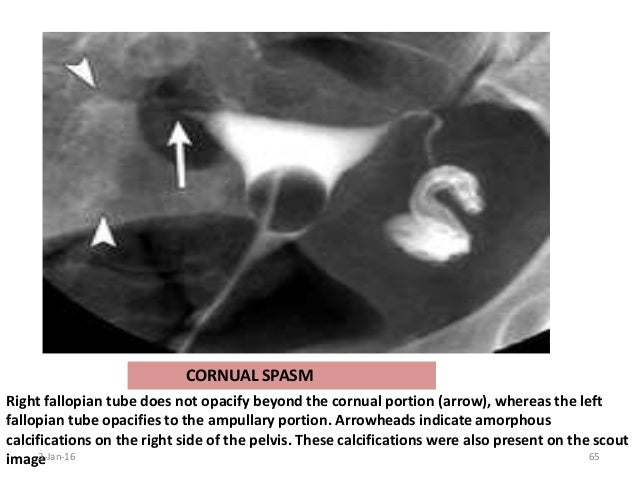

Source : pinterest.com